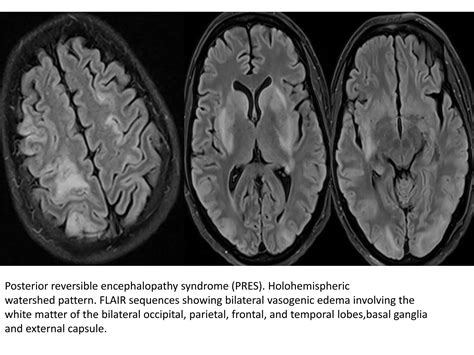

• toxic metabolic encephalopathy radiology